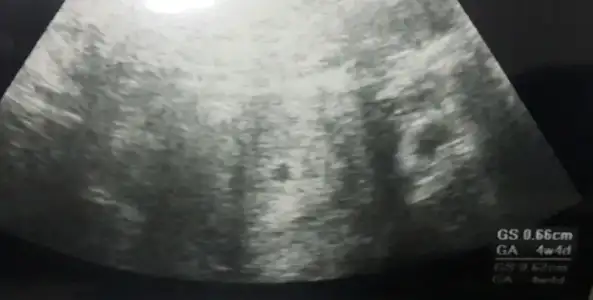

8 mart sali gunu yapilan ultrason bu cnm. Burda yazio 4+4 die

Eklentiler

• Screenshot_2016-03-08-22-53-53-1.webp

Screenshot_2016-03-08-22-53-53-1.webp

11,4 KB · Görüntüleme: 60